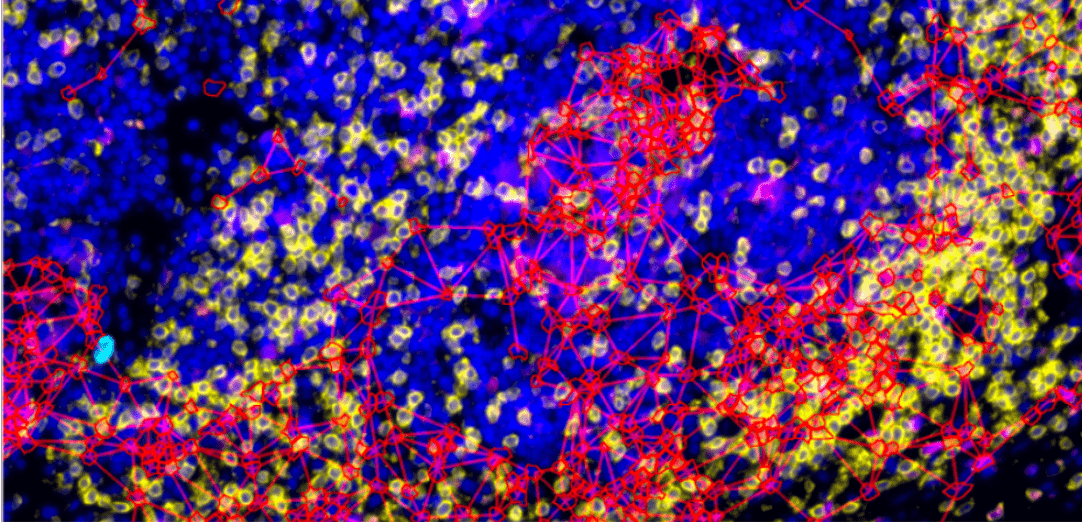

細胞鄰近性測量(Cellular Neighborhood)、空間關係分析,揭示組織微環境複雜交互作用

- 空間關係分析:量化細胞間距離、密度和分佈模式

- 表型交互作用:分析不同細胞亞群之間的空間關聯性

- Network Detection:血管、神經元等網狀結構的自動識別